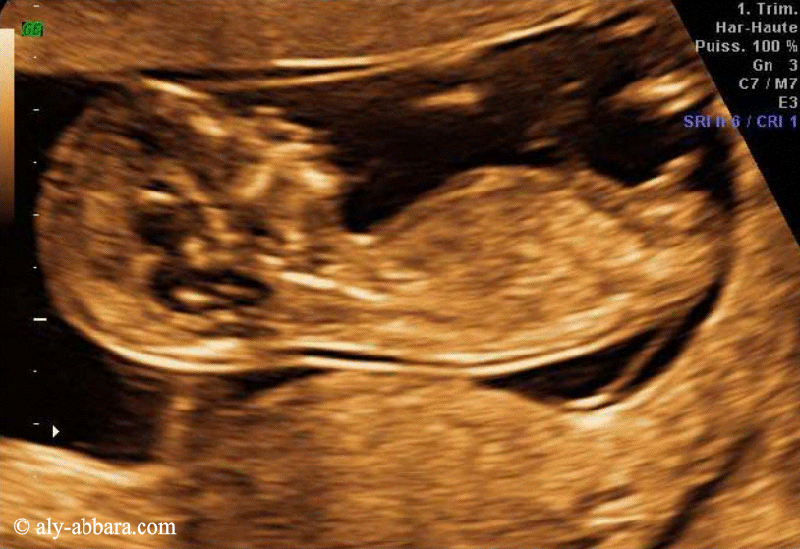

Afin de réduire le nombre de fausses grossesses prolongées par l'imprécision de la date du début de grossesse (DDG), il est fortement recommander de déterminer la date du début de la grossesse par le recours à la mesure échographique de la longueur crânio-caudale fœtale (LCC) entre (11+0SA et 13+6SA) ce qui correspond à une mesure de la (LCC) située entre 45 et 84 mm.

- Critères de qualité de la mesure de LCC sont :

- La coupe fœtale occupe > 50 % du champ de l'image.

- La coupe fœtale est sagittale.

- La position fœtale est neutre (ni en hyperflexion ni en hyperdéflexion).

- L'extrémité céphalique fœtale est dégagée.

- L'extrémité caudale fœtale est dégagée.

- Les

curseurs sont biens placés.